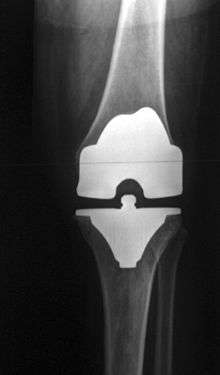

Knee replacement, also known as knee arthroplasty, is a surgical procedure to replace the weight-bearing surfaces of the knee joint to relieve pain and disability. It is most commonly performed for osteoarthritis,[1] and also for other knee diseases such as rheumatoid arthritis and psoriatic arthritis. In patients with severe deformity from advanced rheumatoid arthritis, trauma, or long-standing osteoarthritis, the surgery may be more complicated and carry higher risk. Osteoporosis does not typically cause knee pain, deformity, or inflammation and is not a reason to perform knee replacement.

Knee replacement surgery can be performed as a partial or a total knee replacement.[2] In general, the surgery consists of replacing the diseased or damaged joint surfaces of the knee with metal and plastic components shaped to allow continued motion of the knee.

The surgery involves exposure of the front of the knee, with detachment of part of the quadriceps muscle (vastus medialis) from the patella. The patella is displaced to one side of the joint, allowing exposure of the distal end of the femur and the proximal end of the tibia. The ends of these bones are then accurately cut to shape using cutting guides oriented to the long axis of the bones. The cartilages and the anterior cruciate ligament are removed; the posterior cruciate ligament may also be removed[20] but the tibial and fibular collateral ligaments are preserved. Metal components are then impacted onto the bone or fixed using polymethylmethacrylate (PMMA) cement. Alternative techniques exist that affix the implant without cement. These cement-less techniques may involve osseointegration, including porous metal prostheses.

Femoral replacement

A round ended implant is used for the femur, mimicking the natural shape of the joint. On the tibia the component is flat, although it sometimes has a stem which goes down inside the bone for further stability. A flattened or slightly dished high density polyethylene surface is then inserted onto the tibial component so that the weight is transferred metal to plastic not metal to metal. During the operation any deformities must be corrected, and the ligaments balanced so that the knee has a good range of movement and is stable and aligned. In some cases the articular surface of the patella is also removed and replaced by a polyethylene button cemented to the posterior surface of the patella. In other cases, the patella is replaced unaltered.